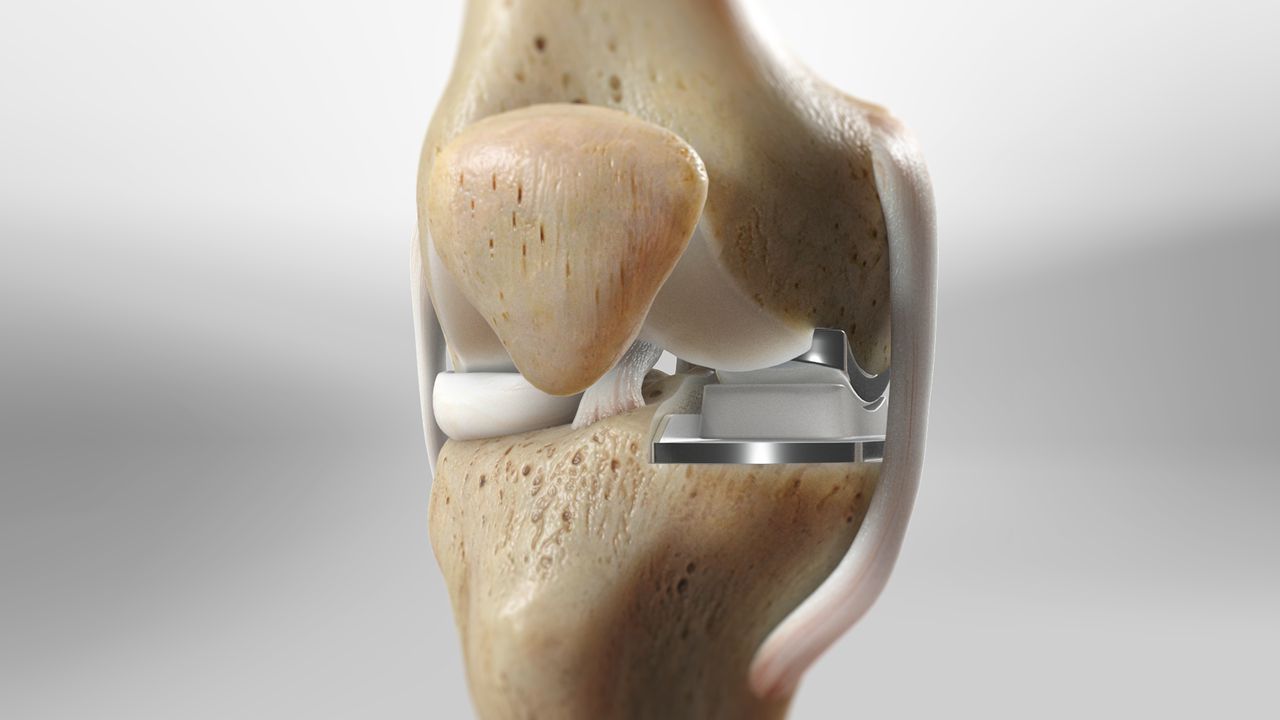

During a total knee replacement surgery, the damaged bone and cartilage are removed from the knee joint and replaced with artificial components. These components typically include a metal femoral component, a metal and plastic tibial component, and a plastic patellar component. The artificial parts are designed to mimic the natural movement of the knee, allowing for improved function and reduced pain. The surgery involves making an incision over the knee, removing the damaged tissue, and securing the new components to the bone using specialized cement or other fixation methods.

During the surgery, the orthopedic surgeon makes a small incision over the knee and removes the damaged bone and cartilage from the affected compartment. These are then replaced with metal and plastic components designed to mimic the natural movement of the knee. The goal is to relieve pain and improve function while maintaining as much of the natural knee structure as possible. One of the significant advantages of partial knee replacement is that it is less invasive than total knee replacement, resulting in a shorter hospital stay, faster recovery, and less postoperative pain.

Partial and total knee replacements are surgical procedures designed to alleviate pain and restore function in patients with severe knee arthritis, but they differ significantly in their approach and scope. This procedure is less invasive, preserving more of the patient's natural knee structures, including the ligaments. In contrast, total knee replacement involves replacing all three compartments of the knee: the medial, lateral, and patellofemoral (front) compartments. This procedure is recommended for patients with widespread arthritis affecting the entire knee joint. During the surgery, the damaged bone and cartilage are removed and replaced with metal and plastic components designed to mimic the natural movement of the knee.